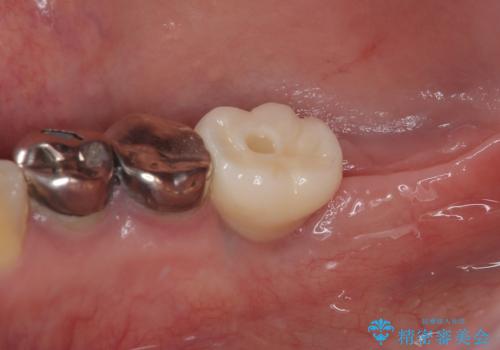

インプラント早期荷重について

インプラント早期荷重とは、通常よりも短い期間で人工の歯を装着し、早い段階で噛めるようにする治療方法です。

従来は数か月間待つ必要がありましたが、骨の状態や全身状態が良好な場合には、条件を満たせば早期に仮歯や最終の歯を入れることが可能です。

これにより

・治療期間の短縮

・見た目の回復が早い

・食事や会話の不便さを早く改善できる

といったメリットがあります。